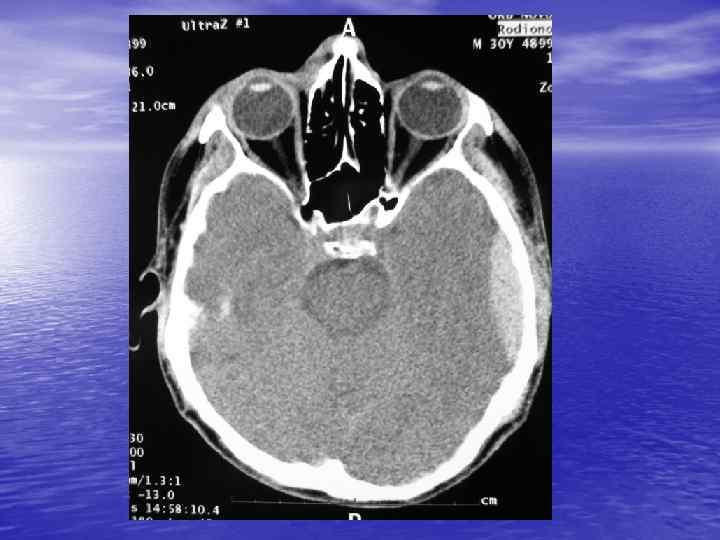

С появлением компьютерного томографа стало возможным визуализировать тканевые структуры головного мозга

Преимущества спиральной КТ: ü Возможность проведения исследования с болюсным ü ü ü ü ü контрастированием Высокая разрешающая способность; Высокая скорость исследования; Получение высококачественных изображений костных структур; Возможность обследования всего тела; Возможность проведения исследования больных под наркозом; Возможность детальной оценки состояния крупных и периферических сосудов в условиях искусственного контрастирования; Высокая информативность метода при черепномозговых травмах в остром периоде; Ранняя диагностика ишемических и геморрагических инсультов; Метод выбора для диагностики заболеваний легких; Планирование лучевой терапии.

недостатками КТ являются: ü Высокая лучевая нагрузка на пациента. ü Необходимость применения ü ü водорастворимых йодсодержащих контрастных препаратов. Отсутствие визуализации спинного мозга. Затруднение визуализации задней черепной ямки, краниовертебрального перехода.